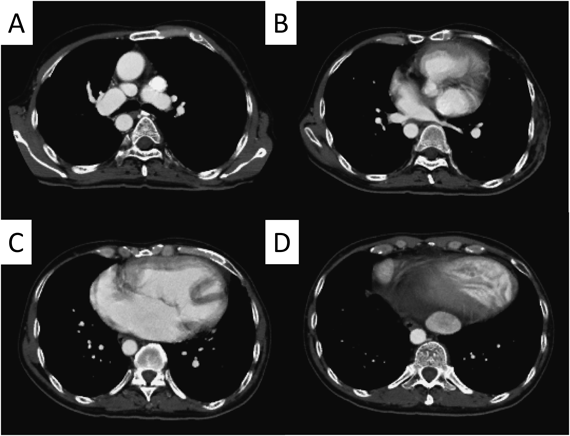

造影CT検査

心房心室ともに拡大所見を認めた.上下大静脈は心尖同側の左側心房に還流,肝静脈はすべて下大静脈に還流し,両側肺静脈は右側心房に還流していた.下大静脈の拡大所見を認めた(Fig. 3).以前施行された左体肺動脈短絡手術に用いられた人工血管は閉塞していた.3D-CTでは,肺動脈は蛇行屈曲を認め,左右肺動脈分岐部にも狭窄を認めた(Fig. 4).

Fig. 3 Preoperative computed tomography (CT)

(A) Preoperative CT angiogram showing the superior vena cava located on the left side. (B) All pulmonary veins returned to the right side of the atrium. (C) Large atrium and dilated right ventricle. (D) Cardiac apex and inferior vena cava were located on the left side.